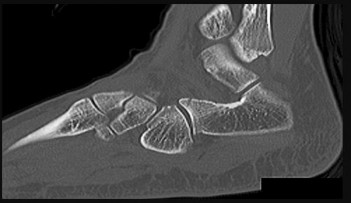

Question 15:

A 58-year-old man with long-standing diabetic peripheral neuropathy presents with a swollen, erythematous, and warm right foot without ulcerations. He reports minimal pain but his midfoot arch has collapsed over the past month. Radiographs demonstrate fragmentation, periarticular debris, and subluxation at the tarsometatarsal joints. Which of the following is the most appropriate initial management for the acute phase of this condition?

This patient is presenting with acute Eichenholtz Stage I Charcot arthropathy (fragmentation stage). The hallmark of treatment for acute Charcot neuroarthropathy is strict offloading and immobilization to prevent further deformity until the active inflammatory process resolves (Stage III - consolidation). Total contact casting is the gold standard for achieving this.